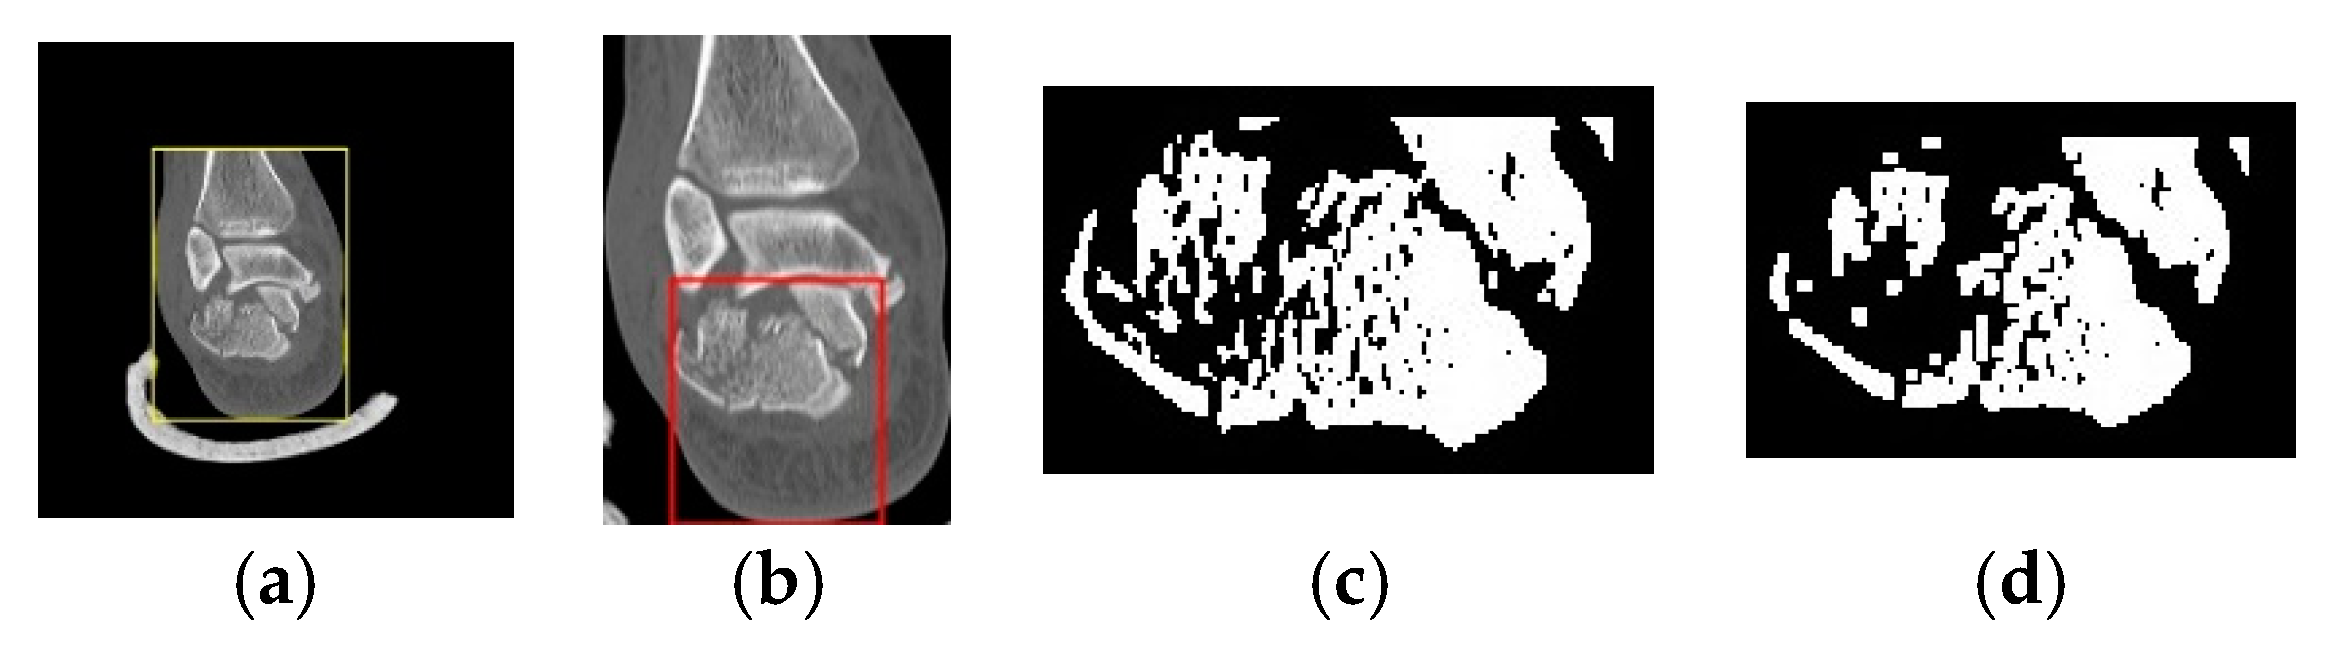

2.5. Step 2: Segmentation of the Calcaneus Fragments

2.5.1. Classification of Calcaneal Fractures in Coronal and Transverse Images